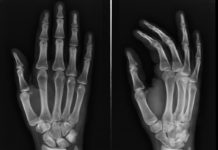

“Dripping Candle Wax” Bone Disease Genetic Cause Uncovered

Melorheostosis is a sporadic disease of uncertain etiology characterized by asymmetric bone overgrowth and functional impairment. It...